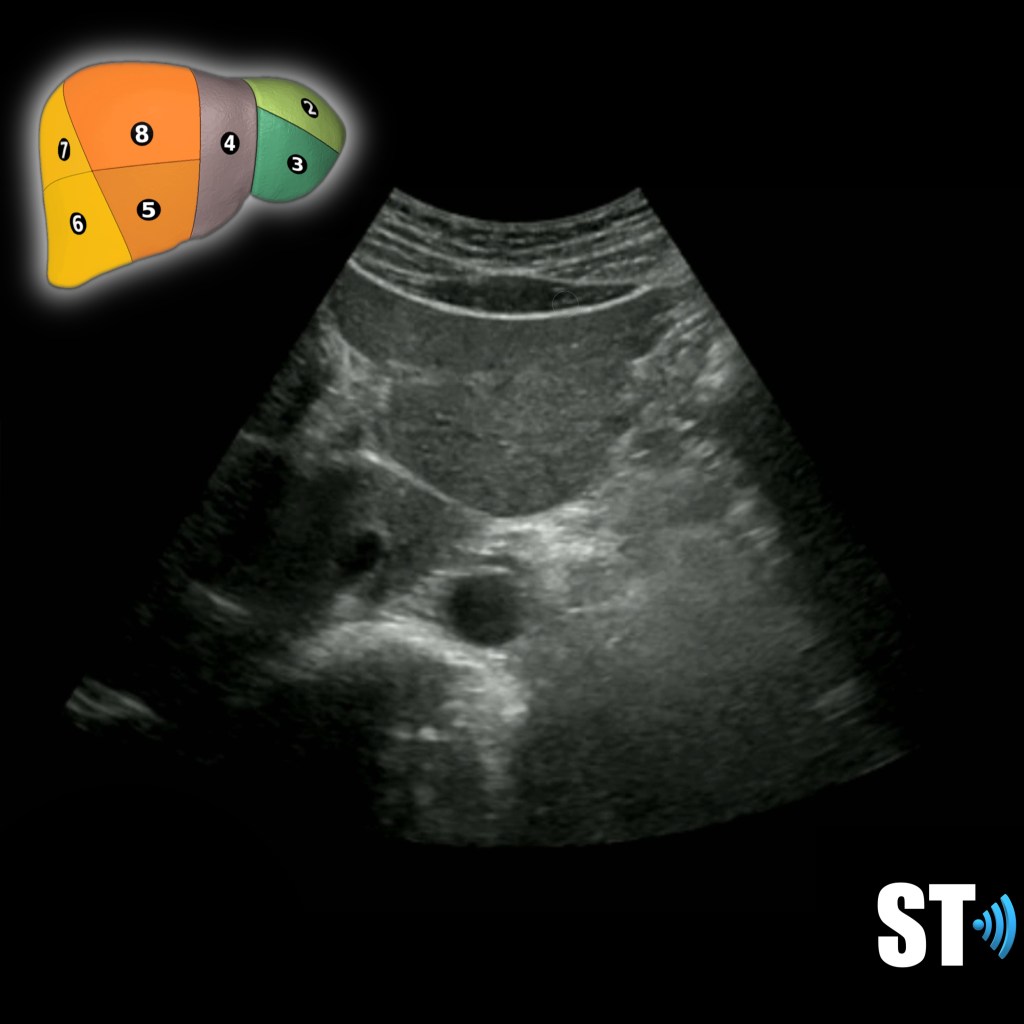

Transverse superior Rt lobe

Segments IVa VII, and VIII